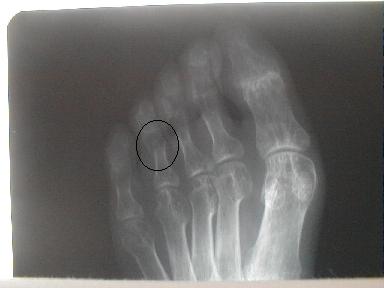

7月19日整復固定後のx-p